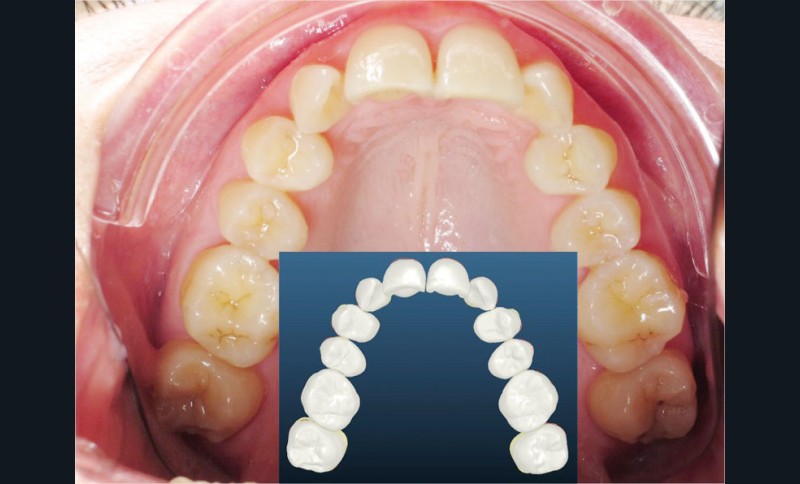

Un appareillage Damon métal a été mis en place, réalisé à partir d’un set up numérique Insignia pour obtenir un contrôle précis des torques et de la forme d’arcade et réduire le temps de finition grâce à un collage indirect très précis.

De larges surélévations postérieures étalées ont été mises en place et la patiente a porté des élastiques précoces suivant les principes de la technique Damon. Les 14 et 24 rempliront le rôle des 13 et 23.

L’objectif, en utilisant la technique Insignia est de réduire le temps de traitement de 28 à 18 mois avec 12 rendez-vous (fig. 5 à 14).